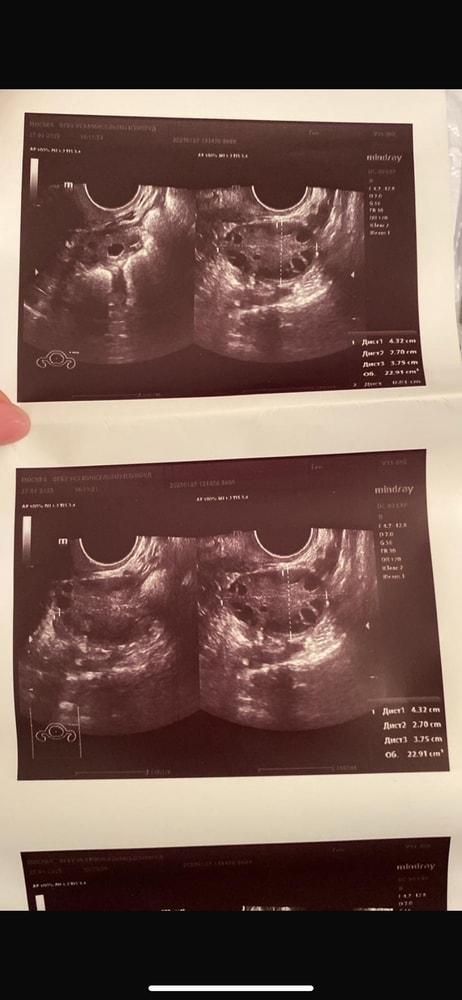

Виктория 5 месяцев Спкя или мфя (узи) Врачи сказали что между спкя и мфя. Посмотрите еще 20 записей на эту тему Лучший ответ Евгения Спкя только по одному узи не ставят, по внешним признакам ( акне , гирсутизм и другие прелести) , цикл, гормоны и тд 21.07.2025 Ответить Отменить Ответить УЗИ Чаты Беременных Выберите чат: Январята-2026 Февралята-2026 Мартята-2026 Апрелята-2026 Майчата-2026 Июнята-2026 Июлята-2026 Августята-2026